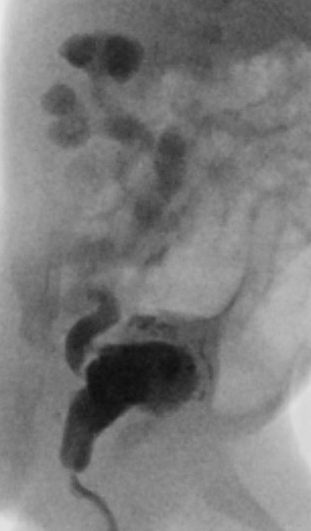

20 weken echografie: links: dikwandige blaas met verwijding van de plasbuis tot aan de kleppen (pijl): het “sleutelgat teken”. Onder: verwijde urineleiders. Bij kinderen gaan de urineleiders bij verwijding ook erg gekronkeld verlopen.

Verwijde nierbekkens (lange pijl) en nierkelkjes (korte pijl). Smalle nierschors.